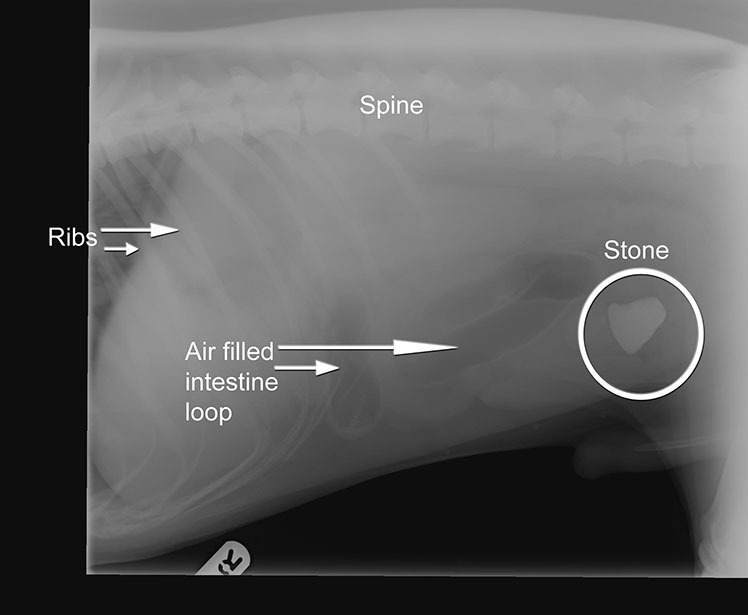

Arky is a gorgeous 9 month old red setter. He presented to us feeling vey poorly and being regularly sick. We admitted him into the practice to do some tests - blood samples and x-rays. The x-ray we took is below.

The white item you can see in his abdomen is a stone! Arky had willingly eaten this stone! It had made its way through his stomach, through the top of his intestines before getting stuck halfway through his guts. At this point things became very serious. If this stone was left where it was Arky would become even more ill. So we took him straight to theatre where we removed the stone surgically.